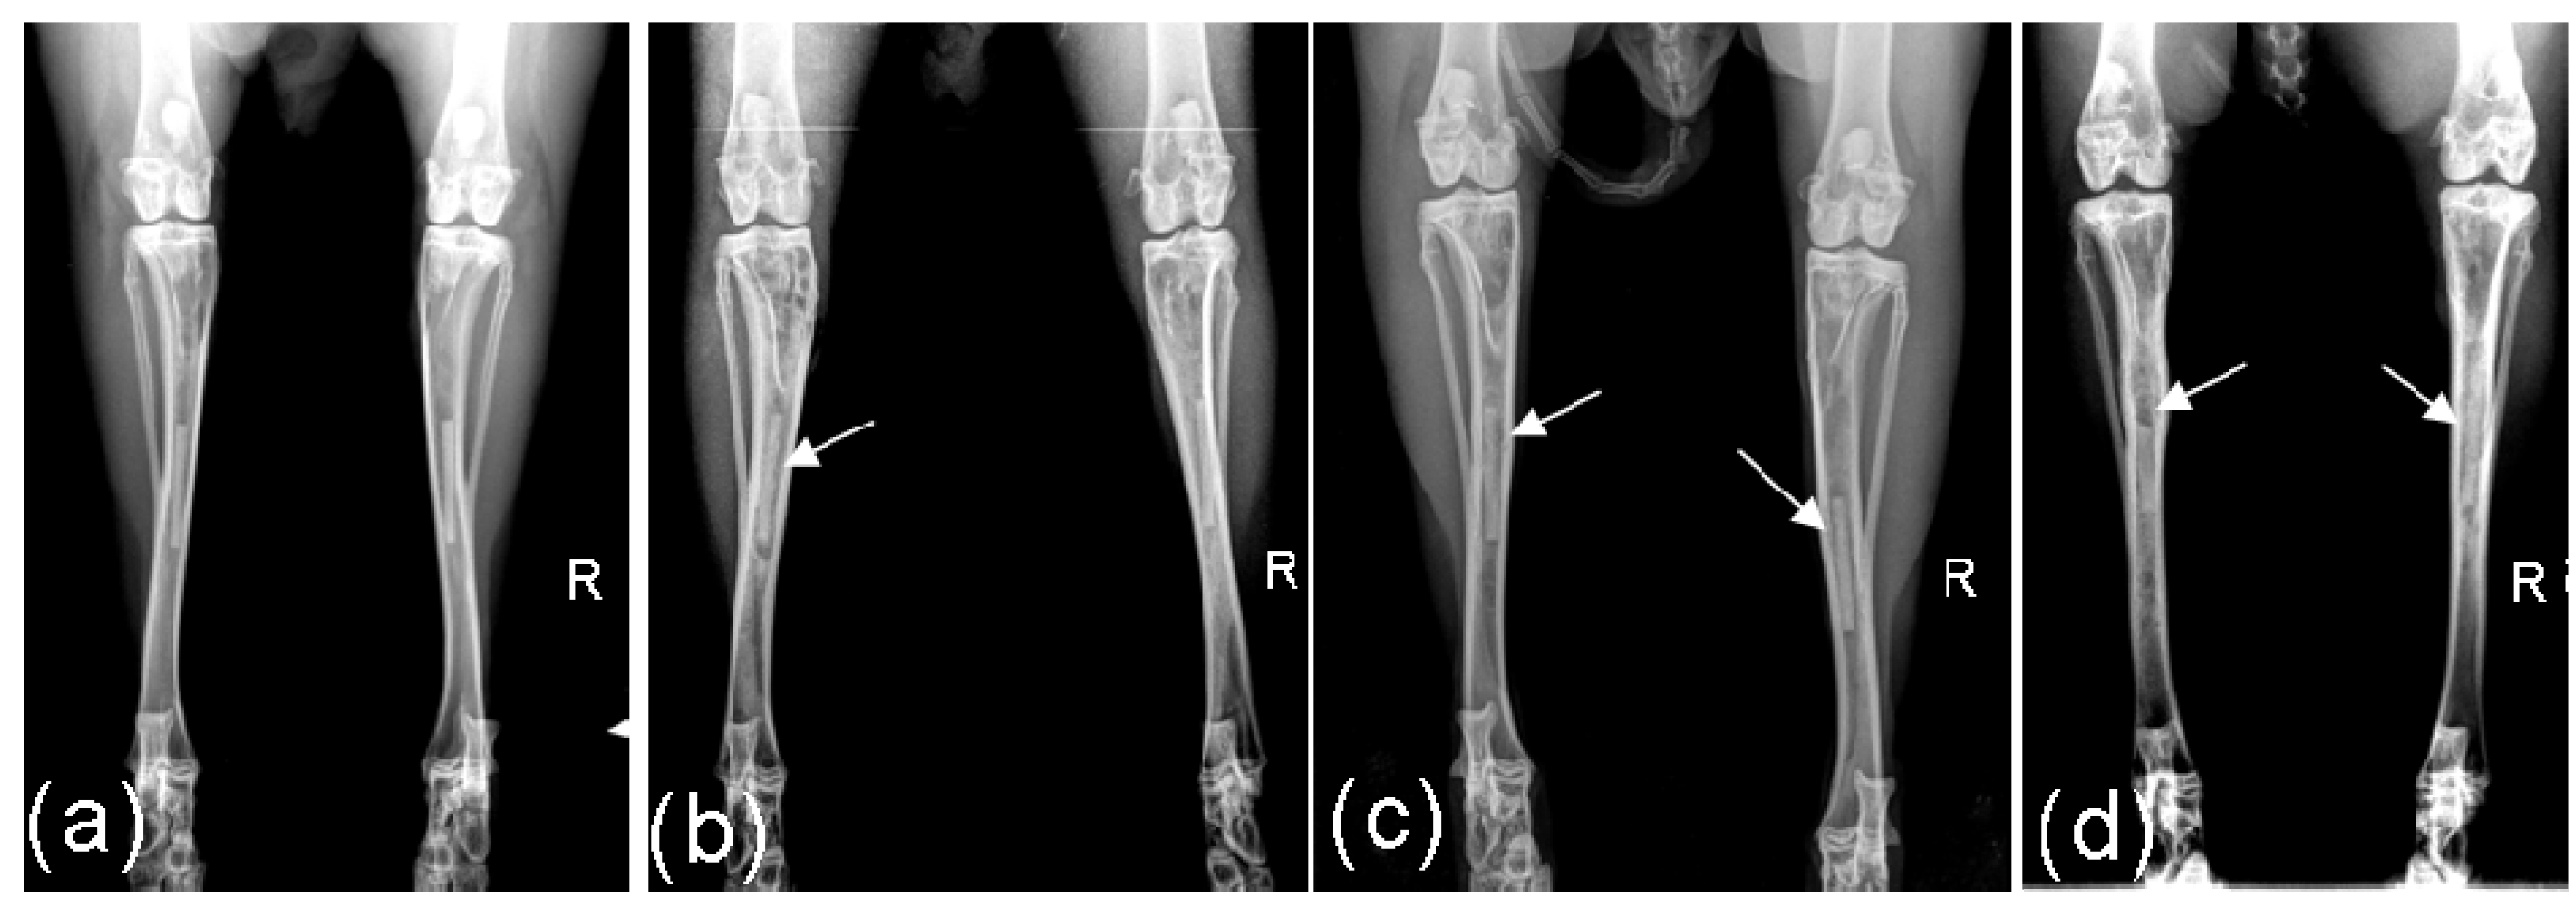

2.2. Radiological Investigations

3.2.4. Radiological Investigation